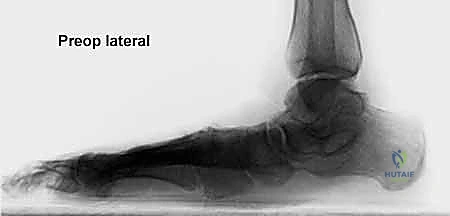

* الأشعة السينية (X-rays) مع تحمل الوزن: ضرورية لتقييم درجة انهيار القوس وزوايا العظام (مثل زاوية تالونافيكولار Meary's Angle).